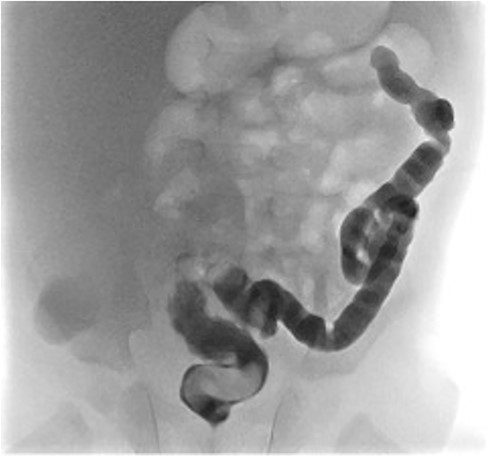

At elective ileostomy closure 2 months later, a colonic stricture was found 5 cm distal to mucous fistula, which was resected. Saline was instilled distal to the excised colonic stricture, which did not progress suggesting further distal obstruction. The decision was made to defer stoma closure at this stage. Subsequent colonoscopy revealed normal distal colon up to the level of the distal transverse colon at which point the colon was completely occluded in a blind ending pouch and on probing with a guide wire no lumen was found. Atresia was confirmed with contrast enema (Fig. 3). At 8 months of age, he underwent laparotomy and resection of a 10 cm section of transverse colonic atresia. Histology reported narrowing of the transverse colon, focal granulation tissue, and mucosal web formation. His recovery and subsequent follow-up have been uneventful.

Contrast enema for case 2 showing complete failure of passage of contrast into distal transverse colon.